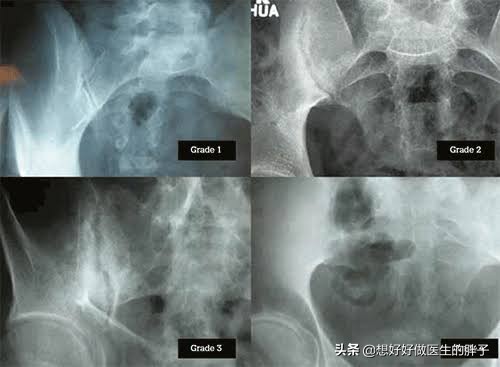

●骶髂关节的x线或者是ct以及核磁检查。因为很多强直性脊柱炎的患者发病就在骶髂关节这个位置,比较严重的患者,在普通x线上就能看到骶髂关节的破坏,但是如果是早期的患者,可能要借助于ct或者是核磁检查,这种比较精密的检查手段,才能更好的发现骶髂关节的问题。